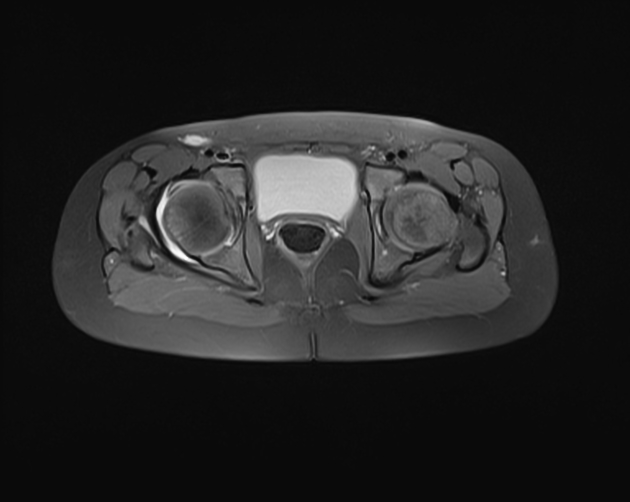

4. MRI

T2영상에서 신호강도가 높은 활액의 증가소견이 관찰됩니다. 대퇴골이나 골반골의 신호강도 변화는 관찰되지 않아야 합니다.